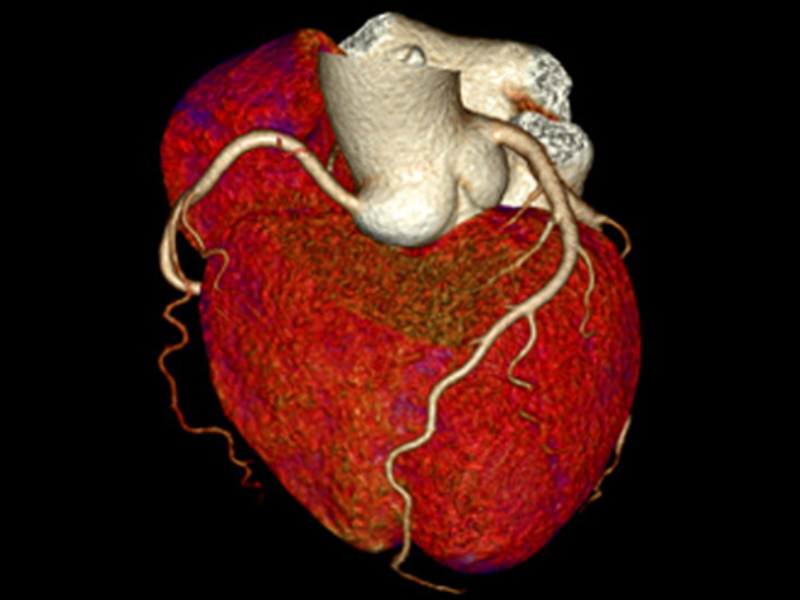

One-Beat Cardiac Scan Severe Arrhythmia 50-215 bpm

Excellence in Cardiac Imaging

Designed to make coronary CTA imaging more robust than ever, the uCT ATLAS is engineered with 0.25s rotation speed, unprecedented 25 ms effective temporal resolution enabled with uAI CardioCapture and an intelligent cardiac workflow.